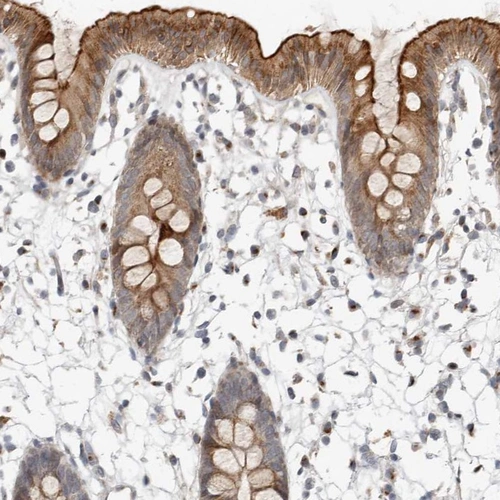

Immunohistochemical staining of human colon shows strong membranous and cytoplasmic positivity in glandular cells.